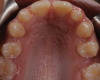

A 16-year-old female patient presented with the chief complaint that she was dissatisfied with the appearance of her anomalous maxillary lateral incisors (teeth Nos. 7 and 10) and multiple diastemas (Figure 1 through Figure 4). She had been referred for restorative treatment after an initial consultation with the orthodontist. Her first restorative appointment was dedicated to data collection, which included a health history and physical examination as well as the acquisition of photographs (facial, dentofacial, dental), videos (chief complaint, F sound, S sound), vinyl polysiloxane (VPS) impressions, a panoramic radiograph, a bite registration, and a facebow registration. The clinical examination revealed that both of the patient's maxillary lateral incisors were peg-shaped. After a discussion about the risks and benefits of different treatment options, such as direct composite restoration, indirect composite veneers, and porcelain laminate veneers, she chose to have her maxillary lateral incisors treated with direct composite buildup restorations. The index cutback technique was chosen for this case instead of a freehand technique in order to create a new shape according to an ideal wax-up but also to be able to control the thickness of the enamel layer.7

(4.) Pretreatment retracted occlusal photograph showing the multiple diastemas.

Figure 4